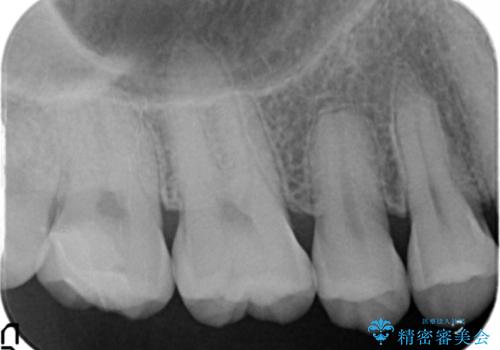

精査したところ、神経近くに及ぶ大きなう蝕を認めました。

神経をとらずに済むよう丁寧にう蝕を除去したのち、セラミックインレーで修復しました。